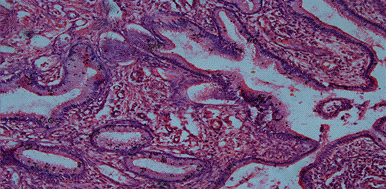

cystic widened glands with dense epithelium and partly swollen dense stroma may be observed.papillary pseudoerosion of uterine neck the formation of papillary outgrowths of cylindrical epithelium with eosinophili are observed. Page 5.

5. Papillary outgrowths.